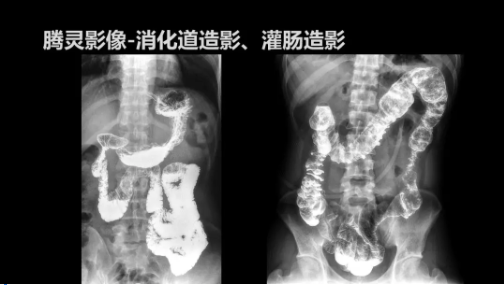

“騰靈”是安健科技的第四代動(dòng)態(tài)DR產(chǎn)品,可實(shí)現(xiàn)全科室應(yīng)用。如各類常規(guī)的X線檢查、消化道檢查、骨科檢查、婦科、兒科檢查等。此外,安健科技為“騰靈”在真正意義上實(shí)現(xiàn)多科室、多功能診斷進(jìn)行了多項(xiàng)針對(duì)性設(shè)計(jì)。

此外,“騰靈”為了能夠幫助醫(yī)生更快速、有效的定位病灶,還增加了多項(xiàng)精準(zhǔn)診斷保障功能,如支持動(dòng)態(tài)觀察診斷,實(shí)時(shí)高清點(diǎn)片等?!膀v靈”透視切換高清點(diǎn)片曝光,捕捉關(guān)鍵病灶診斷僅需0.8s,同時(shí)還支持圖像局部放大,醫(yī)生可自由切換15’12’和9’三種放大模式,另外,“騰靈”還支持視頻保存、回放功能,幫助醫(yī)生在檢查結(jié)束后通過回放查看細(xì)節(jié),為醫(yī)生的診斷增加信心。